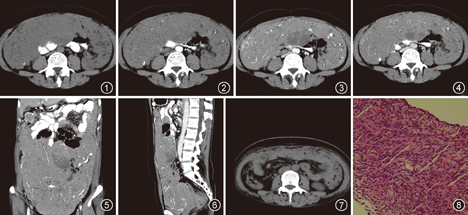

患者 女,46岁。乏力伴全腹胀痛不适3个月,加重1个月。体检:腹部膨隆,自剑突至盆腔触及一巨大肿块,质地中等,位置固定,边界不清,双下肢水肿。血常规及血液生化检查未见明显异常。行全腹CT平扫+增强扫描,平扫示腹腔内弥漫团块状软组织密度影,邻近肠管结构受压改变(图1)。增强扫描肿块轻度延迟强化,肿瘤内可见斑片状无强化坏死区(图2,图3,图4),冠状面、矢状面像示肿块上达肝下缘,下至盆腔(图5, 图6)。行腹腔肿物穿刺活检,术后病理(腹腔穿刺组织)结果提示胃肠间质瘤。给予格列卫药物治疗2个月,腹部胀痛症状好转。复查CT平扫示腹腔内弥漫软组织肿块影较前明显缩小,局部密度欠均匀(图7)。

患者行手术治疗,剖腹探查见肿瘤占据整个腹腔,上方嵌于胃、胰腺及脾之间,上腹部脏器受压移位,肿瘤下方长入盆腔。切除肿瘤,大小为45 cm×39 cm×6 cm,质量为5.2 kg,浸润胃浆膜和大网膜,表面呈结节状,切面呈分叶状、鱼肉样、灰白色、质脆。显微镜下瘤细胞为梭形和上皮样,呈轻度异形性(图8)。免疫组织化学结果:波形蛋白、CD117、间质瘤Dog-1、细胞增殖Ki-67(约40%)、肌动蛋白小灶区阳性,CD34、S-100蛋白、钙结合蛋白CR、细胞角蛋白(CK)、CK5/6、间皮瘤抗原-1均为阴性。病理诊断为胃肠间质瘤。患者术后随访11个月,一般状况良好。